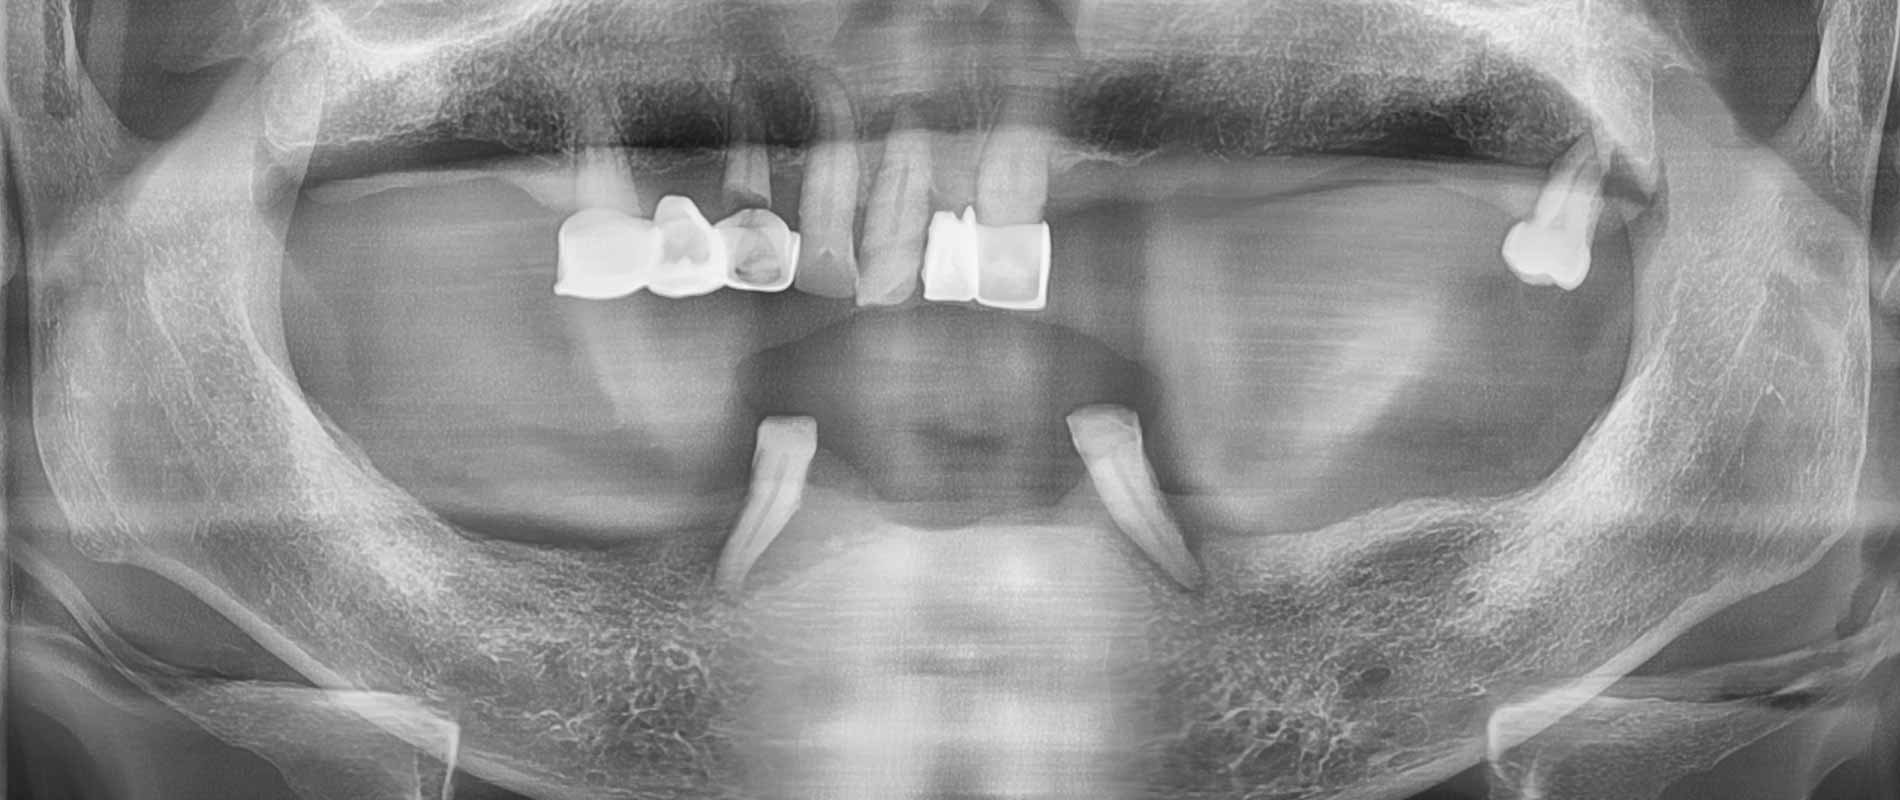

#전체 임플란트 환자 사례 : 17개 임플란트로 찾은 새로운 미소 CT & X-ray

🦷 전체 임플란트 수술 전 후 Case 1

🦷 전체 임플란트 수술 전 후 Case 2